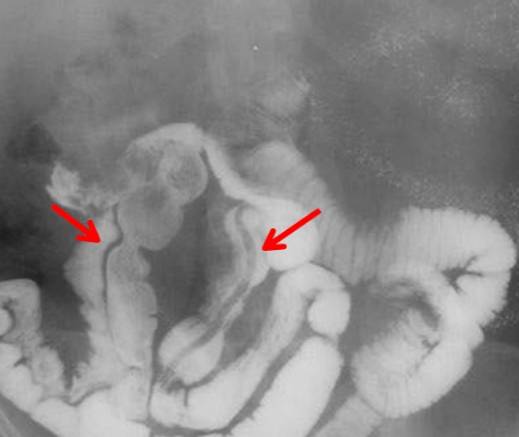

Иногда червя удается обнаружить во время проведения контрастной рентгенографии тонкого кишечника. Он имеет вид светлых полос.Что касается общего анализа крови, то в нем можно обнаружить увеличение числа эозинофилов, лейкопению и анемию. Однако эти показатели являются проходящими.

Иногда червя удается обнаружить во время проведения контрастной рентгенографии тонкого кишечника. Он имеет вид светлых полос.